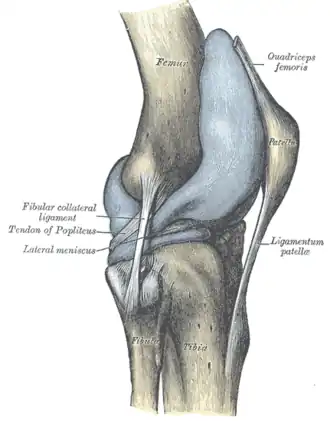

![]() Правый коленный сустав, сбоку. | |

В передней части сустава расположен надколенник (коленная чашечка). Надколенник и четырёхглавая мышца бедра соединены сухожилием, продолжением которого является связка надколенника. В связочный аппарат входят:

- боковые (малоберцовая и большеберцовая коллатеральные)

- задние (подколенная, дугообразная, связка надколенника, медиальная и латеральная поддерживающие)

- внутрисуставные (крестообразные, поперечная связка колена (между менисками)

Суставные поверхности костей покрыты хрящом. Между сочленяющимися поверхностями бедренной и большеберцовой костей имеются внутренний и наружный мениски, представляющие собой серповидные (формы полулуний) хрящи. Коленный сустав имеет несколько синовиальных сумок: